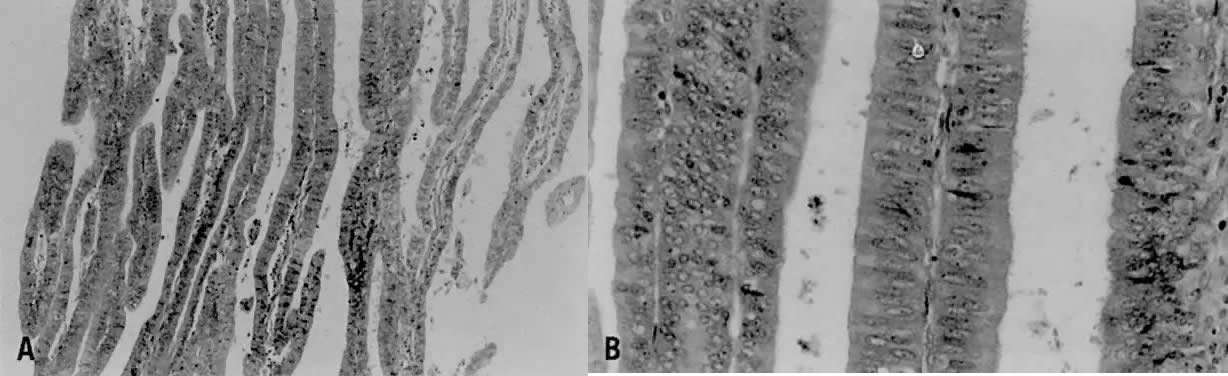

Fig. 6. ( A) Secretory carcinoma is characterized by prominent cytoplasmic vacuoles and intraluminal secretions. ( B) The arrow denotes the uniform subnuclear vacuoles.

Less than 1% of endometrial adenocarcinomas are classified as secretory carcinomas.20 The well-differentiated glands of this variant appear histologically similar to secretory phase endometrium (postovulatory days 3 to 6), with abundantly vacuolated columnar cytoplasm, either subnuclear or supranuclear20,30,31,32,33,34,35 (Fig. 6). Cellular atypia is minimal. Squamous and tubal metaplasia frequently accompany this cell type.20 The adjacent nonmalignant endometrium typically shows changes consistent with prolonged or unopposed estrogen effect (e.g., hyperplasia, stromal breakdown, and thrombosis of vessels). The excellent prognosis seen in these patients is due to the fact that most have surgical stage I disease, and invariably the neoplasm is of low grade both architecturally and cytologically. Distinction from clear cell carcinoma is important due to the marked differences in prognosis. Although both types have intracytoplasmic glycogen, secretory carcinoma does not demonstrate papillary or cystic architecture, nor does it show grade 3 nuclear atypia or the hobnail pattern commonly seen in clear cell carcinoma. Separation of secretory carcinoma from secretory changes in atypical hyperplasia is based on the presence of stromal invasion and back-to-back glands found in carcinoma.